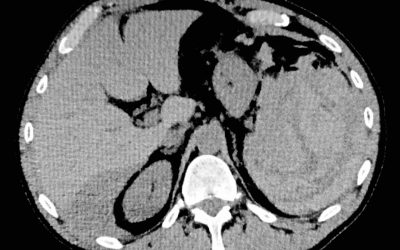

Esiste la rottura spontanea di milza? Un’insolita causa di rottura splenica non traumatica

di Enrico Ganz E’ ben noto che una rottura di milza può manifestarsi “a ciel sereno” in assenza di un evidente trauma. Si identifica questo tipo di rottura con le specificazioni “non traumatica” oppure “spontanea” (1,2,3,4,6). Evidentemente l'uso di questo...